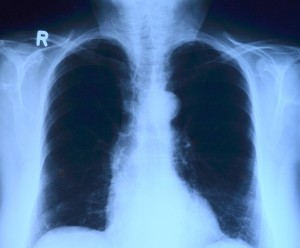

Учёные из Массачусетского технологического института создали портативный датчик, который буквально "нюхает" дыхание и выявляет пневмонию и другие болезни лёгких. Вместо рентгена или долгого ожидания анализов достаточно нескольких минут дыхательного теста, чтобы получить результат.

Эксперименты показали, что датчик способен быстро фиксировать биомаркеры пневмонии даже в очень малых количествах. В будущем такой прибор может появиться как в клиниках, так и у пациентов дома, делая диагностику лёгких простой и быстрой.